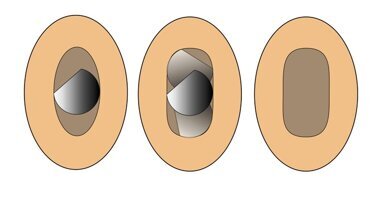

Kako izveštava internet portal MailOnline, prvi korak u ovom novom endodontskom tretmanu bila bi aplikacija antibiotske paste u cilju dezinfekcije inficirane zubne pulpe, dok bi u drugoj poseti nakon petnaest dana specijalnim instrumentom stomatolog napravio male rezove u kanalima korena zuba koji treba da izazovu krvarenje koje bi dovelo do stvaranja krvnog ugruška. Istraživanje je pokazalo da ovaj novostvoreni krvni ugrušak dovodi do stvaranja novih krvnih sudova, što povećava količinu kiseonika i hranljivih materija u kanalu korena zuba i time podstiče reparaciju oštećene zubne pulpe. Iako mehanizam koji dovodi do ove reparacije zubne pulpe nije potpuno razjašnjen, pretpostavlja se da je osnovni razlog prisustvo faktora rasta u krvnom ugrušku, koji podstiče obnovu oštećenog tkiva zubne pulpe.